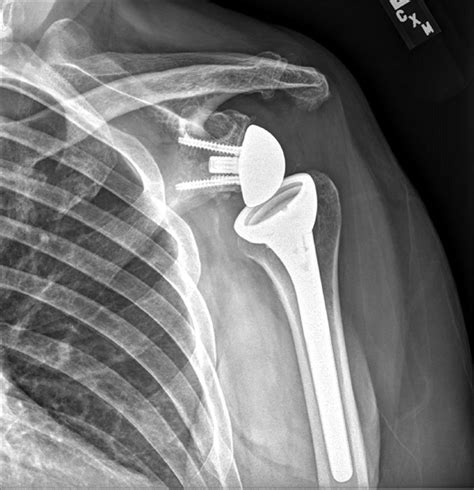

Shoulder replacement surgery, also medically referred to as shoulder arthroplasty, is a surgical intervention where the damaged parts of the shoulder joint are removed and replaced with artificial components, known as prostheses. The shoulder is a ball-and-socket joint, and when the smooth cartilage that allows the bones to glide against each other wears away, the result is painful bone-on-bone contact.

During the procedure, an orthopedic surgeon replaces the humeral head (the ball) with a metal ball and replaces the glenoid (the socket) with a smooth plastic cup. The goal is to eliminate pain and allow the patient to return to normal functioning with a stable and comfortable joint.

• Reverse Total Shoulder Replacement: Designed for patients with severe rotator cuff tears or arthritis where the tendons are irreparable. In this case, the position of the ball and socket is reversed, allowing the deltoid muscle to take over the movement of the arm.